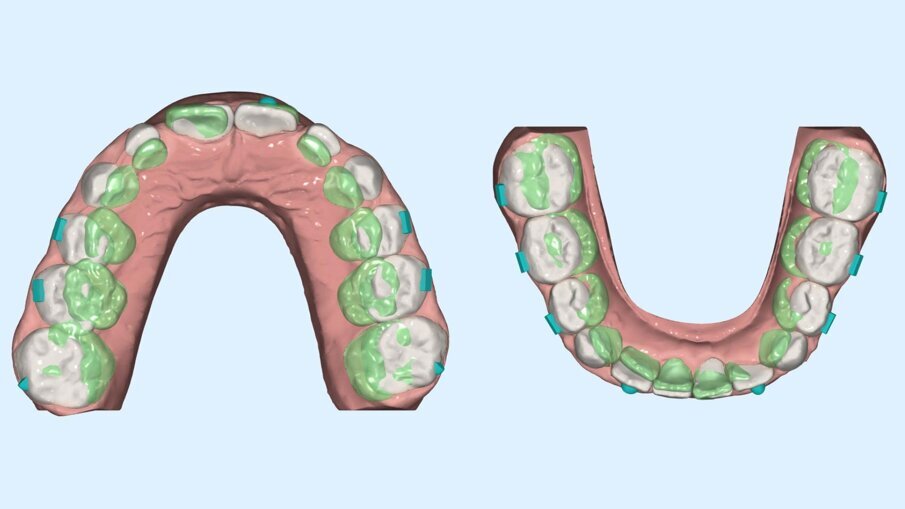

L’ortopantomografia mostrava uno stadio E secondo la classificazione di Demijrian4, affollamento zona apicale nella zona intermedia e anteriore, mentre la teleradiografia laterale confermava la malocclusione di prima classe scheletrica mesodivergente (Figg. 2a-2b). Senza segni né sintomi di problemi basali né respiratori, a circa 24 mesi dal picco puberale, il paziente presentava la necessità di recupero di spazio per lo sviluppo dell’occlusione armonico delle arcate dentarie. La terapia ortodontica precoce con allineatori Nuvola Genius è durata complessivamente 11 mesi ed è consistita in due fasi. La prima di 24 allineatori superiori e inferiori (Fig. 3) e la seconda di rifinitura di 14 allineatori superiori e 12 inferiori.

Fig. 3_Primo set up digitale.

Fig. 4_Programmazione dei movimenti di ottimizzazione trasversale.

Fig. 5_Confronto prima e dopo della programmazione per controllo dei movimenti posteriori.

Fig. 6_Confronto prima e dopo della programmazione sul piano trasverso.